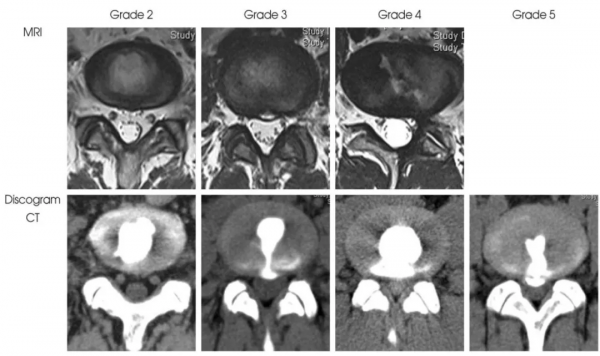

纖維環破裂分級MRI及造影后CT示意圖

箭頭所指為HIZ高訊號區,是纖維環破裂引起的腰痛明顯的磁共振徵象

(Peng B. Eur Spine J 2006;15(5): 383-87)

但值得注意的是,腰椎MRI閱片看到椎間盤HIZ高訊號區時,不要僅關注T2加權像,也應關注T1加權像。因為只有在T2侷限性高訊號、T1侷限性較低或等訊號(single-HIZ)才意味著通常所指的纖維環破裂伴隨肉芽組織長入,HIZ診斷椎間盤源性腰痛才有指導價值。詳見腰椎間盤HIZ高訊號區 (High-intensity zone)

椎間盤造影后CT平掃所顯示破裂的纖維環(即為疼痛的椎間盤),且造影劑流經至HIZ高訊號區,提示椎間盤源性腰痛的診斷。(Peng B. Spine 2006;31(5): 560-66)